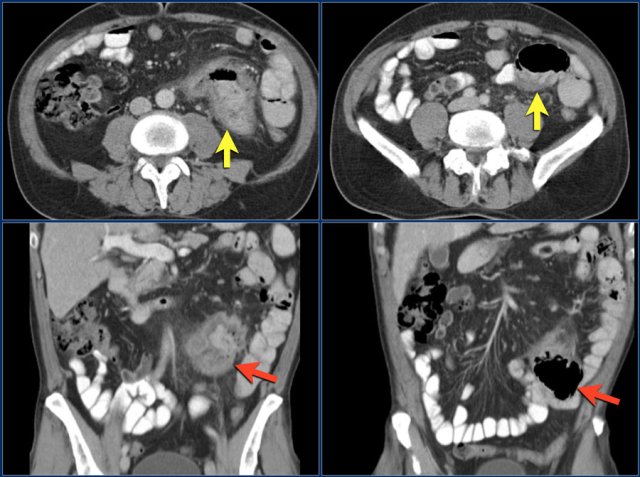

First study the images.

Then continue reading.

The red arrow indicates the sigmoid, which is filled with feces. So this is not a small bowel feces sign.

The findings are:

- Obstructing lesion in the ileum with shouldering leading to small bowel obstruction (yellow arrow).

One could consider the diagnosis of Crohn's disease.

However this patient was not known with Crohn's disease and the terminal ileum (not shown) was normal, which would be uncommon.

At surgery this proved to be an adenocarcinoma.

Here another adenocarcinoma located in the jejunum.

There are multiple lymph nodes (red arrow) and there is fat stranding (yellow arrows).

It should not be mistaken for mesenteric panniculitis as these large necrotic lymph nodes are pathologic.